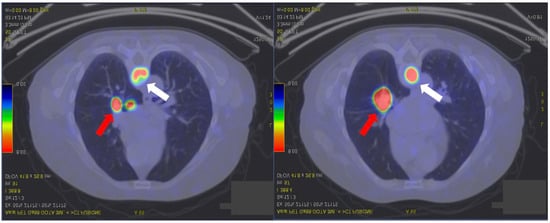

2. Case Presentation